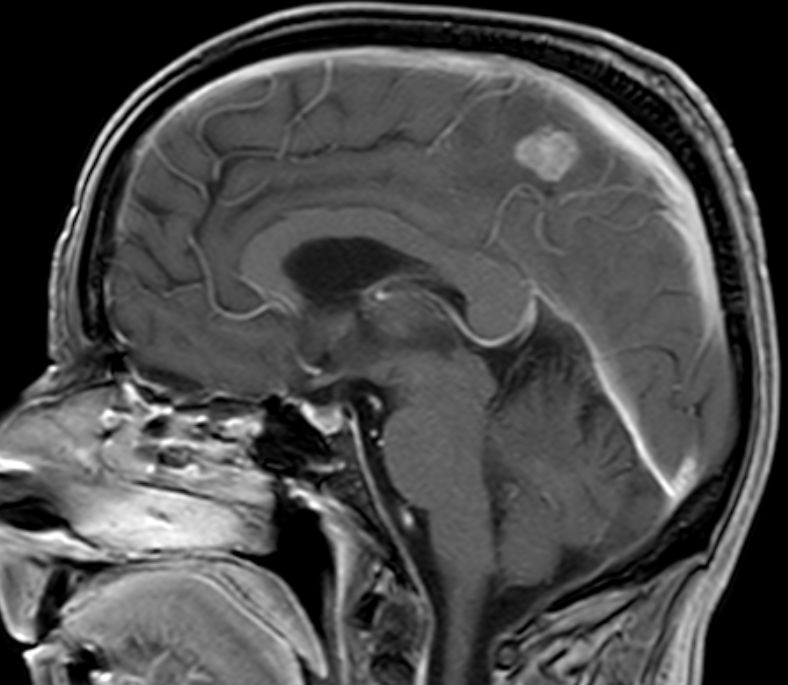

| Hirnmetastasen: Fallbeispiel frühe Hirnmetastasen nach regionalem Rezidiv | 68-jähriger Mann, der vor 4 Monaten ein Melanom des linken Unterschenkels pT1a pN2b M0 mit Metastasen in der linken Leiste hatte. Histologie: Naevus-assoziierte superfiziell, spreizendes Melanom. Nach OP und Defektverschluss verzögerte sich die Strahlentherapie durch ein ausgedehntes Serom. Während der Bestrahlung traten eine Kraftminderung, gesteigerte Reflexe und Sensibilitätsstörungen im rechten Bein auf. Das MRT zeigt 2 Hirnmetastasen. | |||